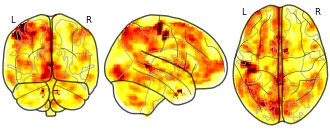

License information was derived automaticallyDescriptionBMIxAllFoodValuation_Value_Beta.nii.gz

Considerable evidence points to a link between body mass index (BMI), eating behavior, and the brain's reward system. However, much of this research focuses on food cue reactivity without examining the subjective valuation process as a potential mechanism driving individual differences in BMI and eating behavior. The current pre-registered study (https://osf.io/n4c95/) examined the relationship between BMI, healthy eating, and subjective valuation of healthy and unhealthy foods in a community sample of individuals with higher BMI who intended to eat more healthily. Particularly, we examined: (1) alterations in neurocognitive measures of subjective valuation related to BMI and healthy eating; (2) differences in the neurocognitive valuation for healthy and unhealthy foods and their relation to BMI and healthy eating; (3) and whether we could conceptually replicate prior findings demonstrating differences in neural reactivity to palatable vs. plain foods. To this end, we scanned 105 participants with BMIs ranging from 23 to 42 using fMRI during a willingness-to-pay task that quantifies trial-by-trial valuation of 30 healthy and 30 unhealthy food items. We measured out of lab eating behavior via the Automated Self-Administered 24 H Dietary Assessment Tool, which allowed us to calculate a Healthy Eating Index (HEI). We found that our sample exhibited robust, positive linear relationships between self-reported value and neural responses in regions previously implicated in studies of subjective value, suggesting an intact valuation system. However, we found no relationship between valuation and BMI nor HEI, with Bayes Factor indicating moderate evidence for a null relationship. Separating the food types revealed that healthy eating, as measured by the HEI, was inversely related to subjective valuation of unhealthy foods. Imaging data further revealed a stronger linkage between valuation of healthy (compared to unhealthy) foods and corresponding response in the ventromedial prefrontal cortex (vmPFC), and that the interaction between healthy and unhealthy food valuation in this region is related to HEI. Finally, our results did not replicate reactivity differences demonstrated in prior work, likely due to differences in the mapping between food healthiness and palatability. Together, our findings point to disruptions in the valuation of unhealthy foods in the vmPFC as a potential mechanism influencing healthy eating.